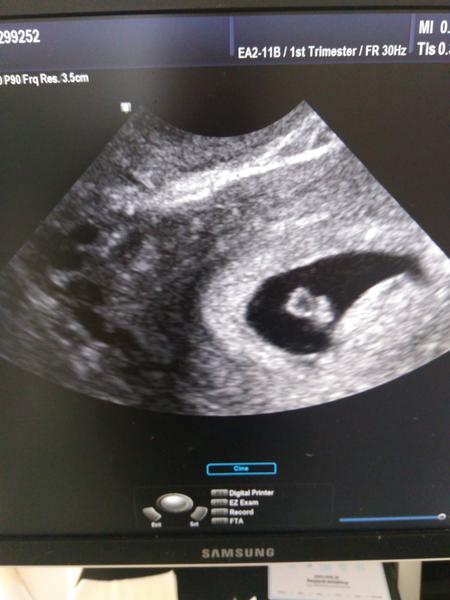

@lapaloma1987 nie ja dom odfotila do mobilu 😁 hcg som mala 12dpt 236 a 24dpt 18774 😁 ale 16fpt už bolo na usg vidno gestacny vak 3mm..💖